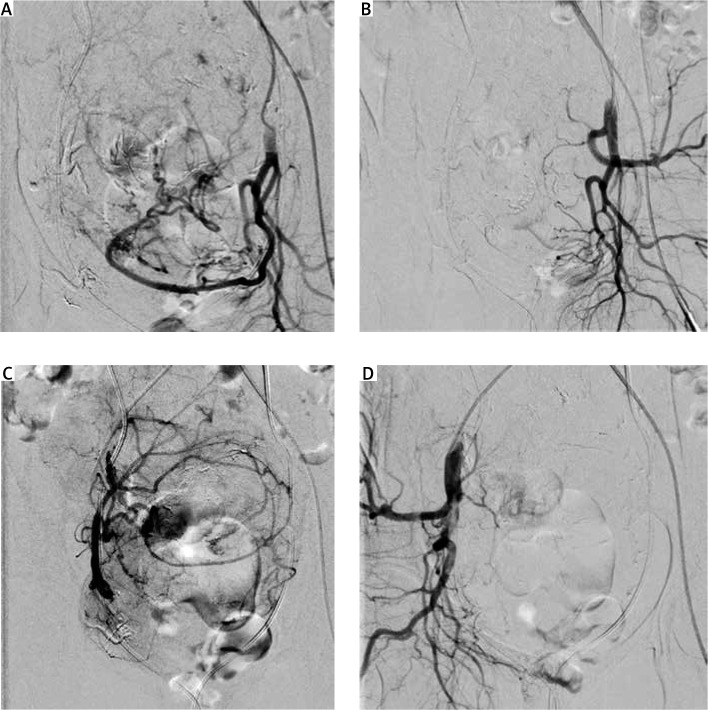

Uterine fibroids are the most common pelvic benign tumours occurring in women of reproductive age. Current treatment options include surgical procedures, pharmacological therapies, and minimally invasive procedures. The most commonly applied and accepted minimally invasive procedure used in the treatment of symptomatic uterine fibroid is uterine artery embolisation (UAE). Uterine artery embolisation is a minimally invasive procedure that can be used either as an auxiliary method or the main treatment method of symptomatic uterine fibroids. We would like to present the application of pre-operative UAE before hysterectomy in anaemic women with giant uterine fibroid (21.9 × 14.9 × 10.4 cm) and HIV-associated nephropathy. Among the possible treatment options for uterine fibroids in cases like the one presented in our manuscript, hysterectomy is the treatment of choice. However, surgical treatment in a patient with severe comorbid conditions and giant uterine fibroid carries serious risk of perioperative complications. Pre-operative UAE decreases such risk by reducing blood loss during hysterectomy and shortening operation/anaesthesia time. Although the benefits of pre-operative UAE before planned myomectomy or hysterectomy in high surgical risk patients with large fibroids has yet to be confirmed in a well-designed clinical trial, this procedure seems to be a promising tool to reduce the risk of perioperative complications in such patients.

Abstract Image